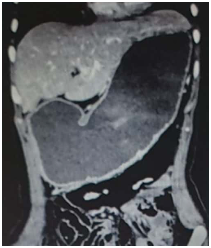

3.4.3. Chụp CLVT Bụng có tiêm thuốc cản quang

- Có giá trị trong chẩn đoán, nguyên nhân , giai đoạn và nhất là trong ác tính